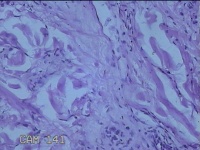

右侧头部息肉结节

性别

男

年龄

39岁

临床诊断

头皮良性肿瘤

一般病史

发现右侧头部息肉结节20余年。

标本名称

右侧头部息肉组织

大体所见

灰白暗红色组织1.2x1x0.8cm一块,表面带梭形皮肤1.2x0.8cm,皮下见结节1.2x0.9x0.3cm一个,切开结节呈实性,切面灰白暗红色,质软。